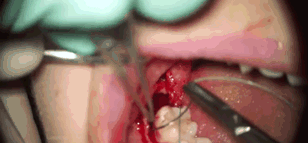

所以赶紧贴心地给他发了拔智齿的GIF

前

方

高

能